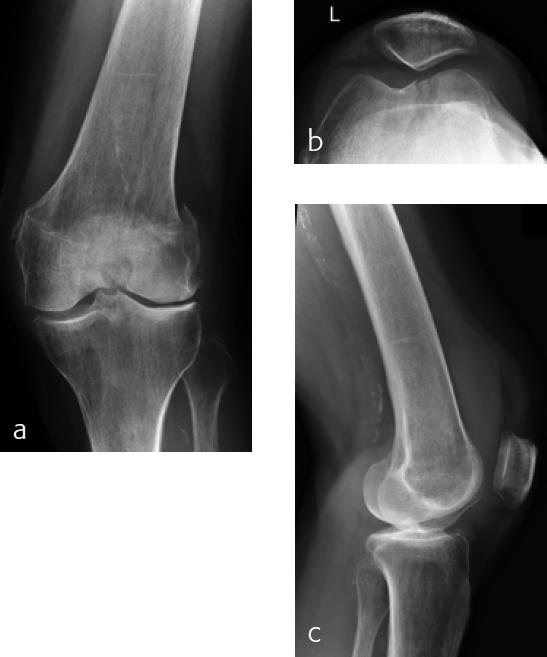

A 79-year-old woman fell downstairs at home and sustained a low-energy distal intraarticular femoral fracture. On conventional x-rays, the fracture seemed to be a unicondylar lateral split-type in rather osteoporotic bone (Fig 1). For detailed fracture analysis, a CT scan was performed that demonstrated a displaced lateral and nondisplaced medial condylar fracture (AO-33C1) (Fig 2). The fracture was very distal and therefore difficult to address with one lateral plate. Using VA technology in this situation provided the advantage of angulating the most distal anterior screw very close to the intercondylar notch in order to address the nondisplaced but fractured anteromedial condyle (Fig 3). Due to poor bone quality, a long plate was used to prevent a future periimplant fracture. Early follow-up showed uneventful healing with good function.